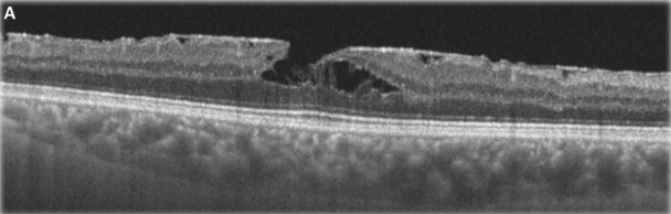

Qual é a classificação do Buraco de Macula?

Classificação de Gass

Estágio 1: Buraco macular iminente

- 1a: Pseudocisto foveal

- 1b: Descontinuidade da retina externa (até 300 micrômetros)

Estágio 2: BM<400 micrômetros + Hialóide aderida à fóvea

Estágio 3: BM > 400 micrômetros + Hialóide solta da fóvea mas permanece aderida ao disco

Estágio 4: BM + DVP completo